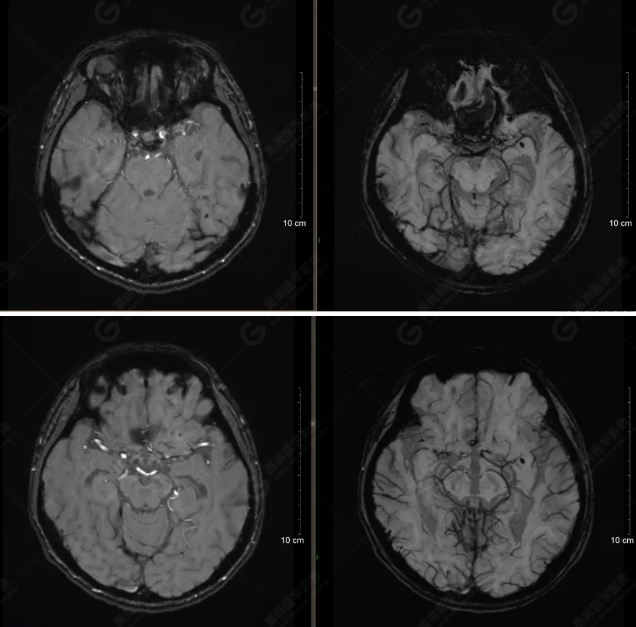

(左側(cè)為薄層原始圖像,右側(cè)為后處理5mm圖像)

SWI序列影像表現(xiàn)及診斷

左側(cè)額底及左側(cè)顳葉內(nèi)見多發(fā)斑點狀極低信號影??紤]額顳葉多發(fā)腦挫傷伴微出血、含鐵血黃素沉著,左側(cè)乳突骨折、乳突內(nèi)積血。討論:1、SWI利用不同組織間磁敏感的差異成像并將其放大,通過檢測病灶中的靜脈分布、出血灶和礦物質(zhì)沉積等,有效改善了相關(guān)疾病的診斷,主要應(yīng)用于中樞神經(jīng)系統(tǒng)。2、根據(jù)磁距圖像和相位圖像表現(xiàn),對于鑒別顱內(nèi)出血及鈣化有一定程度的價值,用于彌補MRI對鈣化顯示的不足。